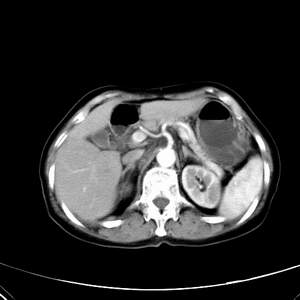

患者,女性,77岁,右上腹胀痛月余。afp正常。ca125升高。即往无肝炎病史。

肝右叶病灶是胆管细胞癌吗?门静脉右支癌栓形成?右侧肾上腺有问题吗?

最后5幅图片是延时7分钟的。门静脉右前支内有充缺吗?如有,肝血管瘤不好解释。

支持:胆管细胞瘤并门脉右支癌栓形成!

考虑胆管细胞癌并门脉右支癌栓形成.

病灶渐进性向心性强化,延时病灶中心见条片状高密度影,局部见肝包膜回缩征,结合病人无肝炎病史,考虑肝右叶胆管细胞癌,门脉右支癌栓形成。